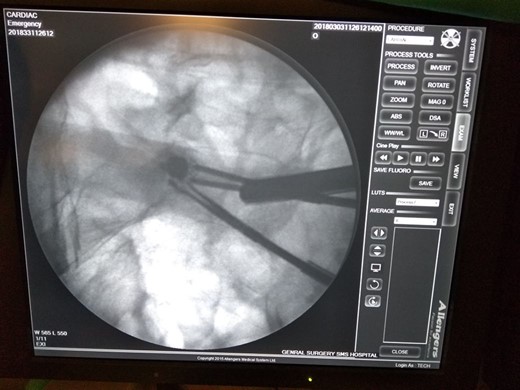

After diagnostic laparoscopy small bowel revealed a stricture in the terminal ileum 3 feet proximal to the ileocecal valve. With the help of C-arm machine video capsule identified (Fig. 2).